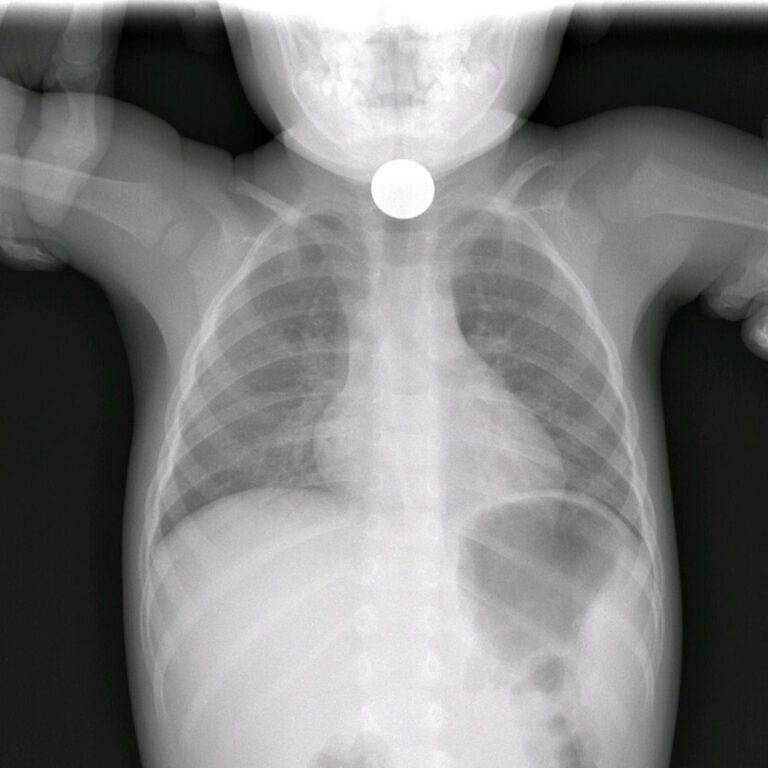

En las vías respiratorias, los cuerpos extraños constituyen una emergencia médica real. Pueden provocar tos intensa, dificultad respiratoria, ruidos al respirar, cambios en la voz, asfixia o incluso pérdida de conocimiento. Entre todos los cuerpos extraños, las pilas de botón se consideran las más peligrosas, ya que pueden causar quemaduras químicas graves y daño tisular en muy poco tiempo, poniendo en riesgo la vida del paciente. Por esta razón, su presencia en la vía respiratoria requiere extracción inmediata y atención médica urgente.